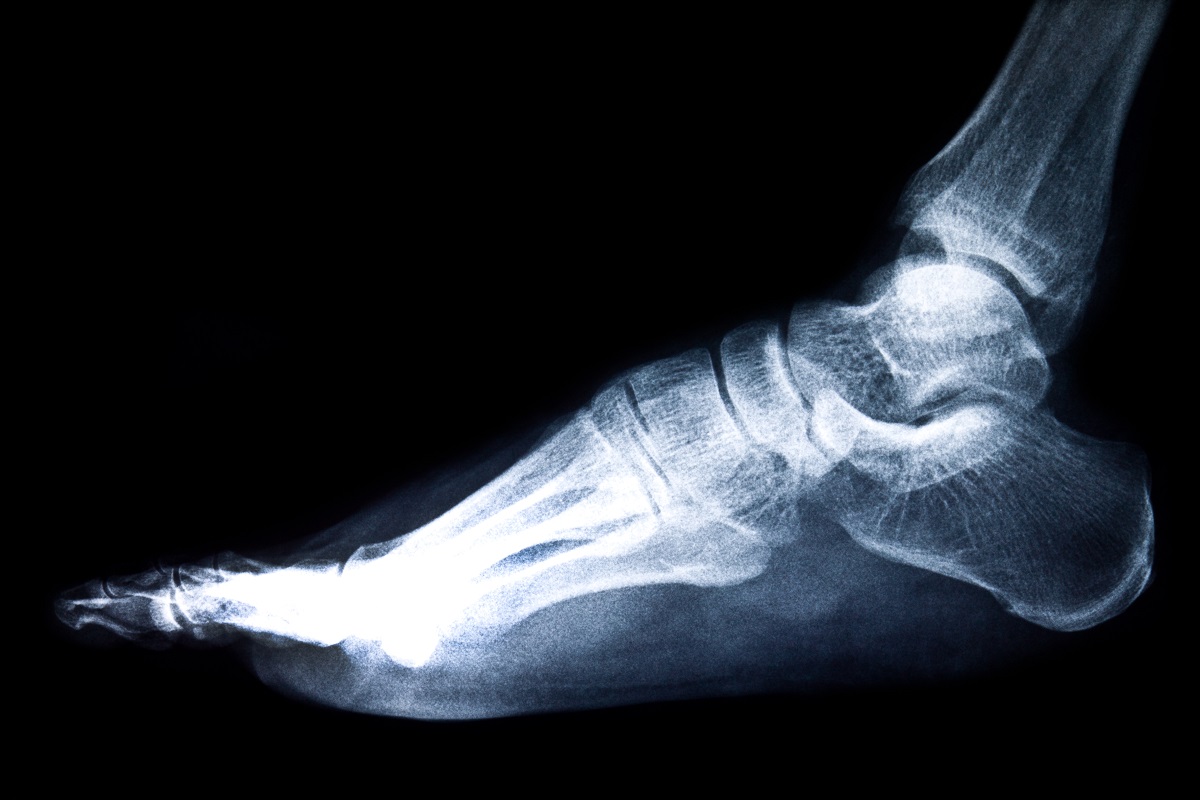

Для постановки точного диагноза врачу скорее всего понадобятся результаты дополнительных исследований. После изучения состояния пациента назначаются такие исследования стопы или голеностопного сустава:

Основные методы диагностики боли в ступне при ходьбе

Методика диагностики Время

Рентгенография стопы 10 минут

КТ стопы 15 минут

МРТ стопы 30 минут

Стоимость обследований, в среднем, колеблется от 1000 до 6000 рублей. Все зависит от локализации боли в ступнях ног в покое и при ходьбе, а также анамнеза недомогания. Врач обычно рекомендует 1-2 обследования для того, чтобы в дальнейшем назначить максимально эффективное лечение.